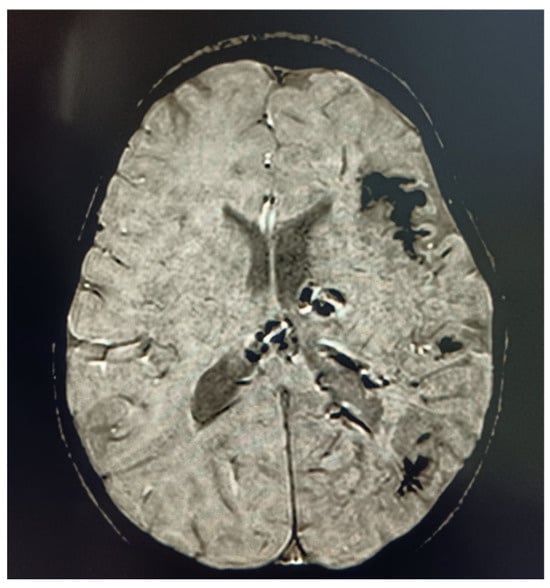

3.3. Diagnostic Work-Up

3.4. Treatment and Manager